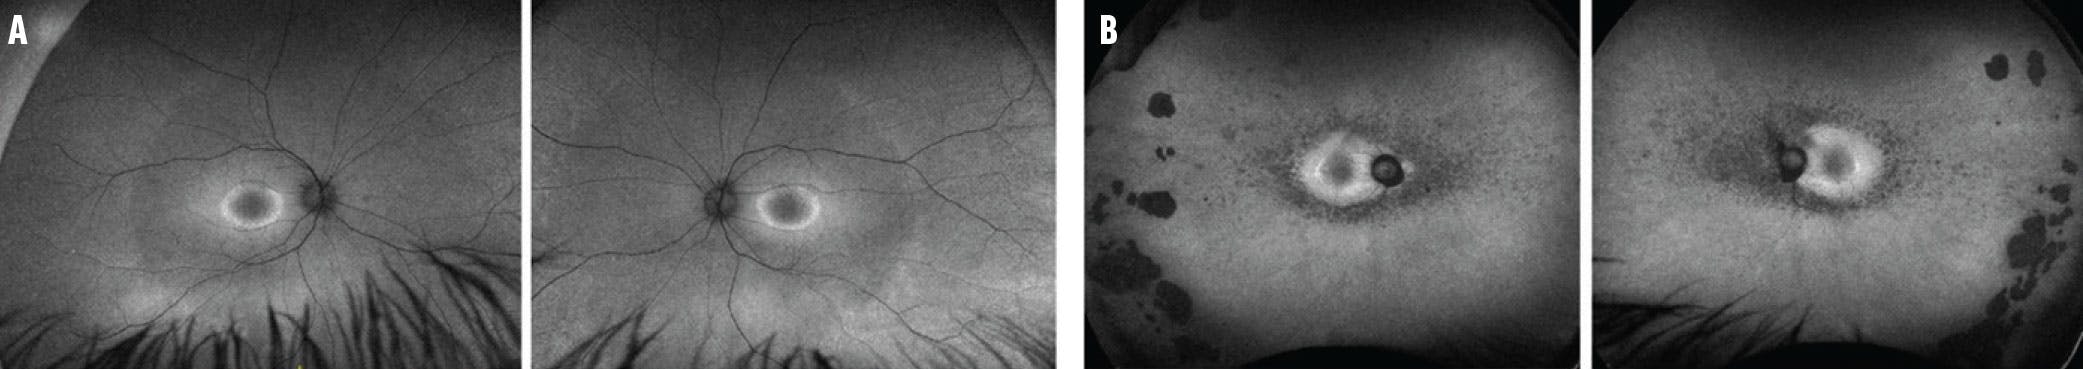

Fundus photography offers the benefit of establishing visible retinal pathology and helps clinicians detect pathognomonic signs and distinguish IRDs from more common conditions such as AMD and inflammatory disorders (Figure 1). Photographs also assist with disease staging. Stargardt disease, the most common macular dystrophy, harbors a staging system based on the presence, extension, and disappearance of retinal flecks and the progression of central atrophy (Figure 2).8 Best disease, the second most common inherited macular dystrophy, has a staging system based on posterior segment changes that correlate with visual acuity.9 Additionally, a hallmark of retinitis pigmentosa (RP), the most common IRD, includes fundus findings such as optic disc pallor, arteriolar attenuation, and bony spicule pigment clumping. Efforts are underway to develop machine-learning algorithms to analyze fundus photographs, which could enhance the sensitivity and efficiency of IRD screening and expedite patient care and diagnosis.7

<p>Figure 1. This 34-year-old man was diagnosed with gyrate atrophy based, in part, on the fundus imaging (A) and UWF fundus imaging (B) of the right eye, which are notable for RPE atrophy with scalloped posterior borders.</p>

Figure 1. This 34-year-old man was diagnosed with gyrate atrophy based, in part, on the fundus imaging (A) and UWF fundus imaging (B) of the right eye, which are notable for RPE atrophy with scalloped posterior borders.